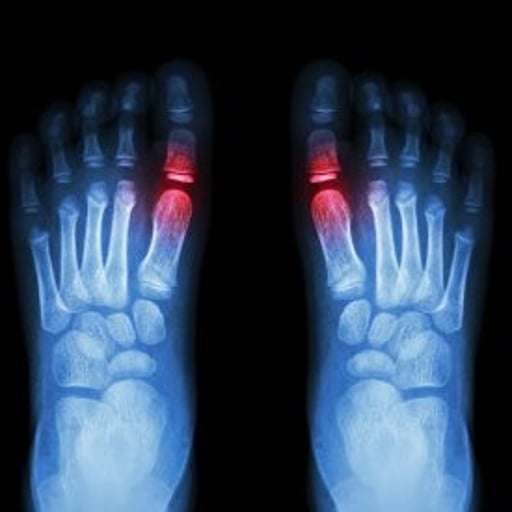

Sesamoiditis

What is Sesamoiditis?

“Pain under the ball of the big toe”

The kneecap (patella) is the largest Sesamoid. Two other very small Sesamoids (about the size of a kernel of corn) are found on the underside of the big toe joint. Sesamoids act like pulleys providing an increase lever arm to the big toe flexor muscles. They glide within their joint, grooves under the big toe joint called Crest, providing a smooth surface over which the tendons slide, increasing the ability of the tendons to transmit muscle forces. The big toe’s sesamoids help the big toe to flex, contract and push giving it more pushing power

Sometimes low dose digital X-ray, low dose fluoroscopy, can help to investigate Sesamoiditis. In some cases haematological tests or a referral to MRI may be required.